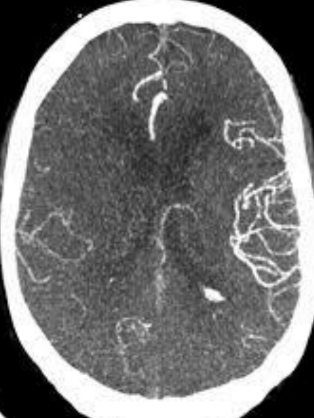

A

MAV angioTC